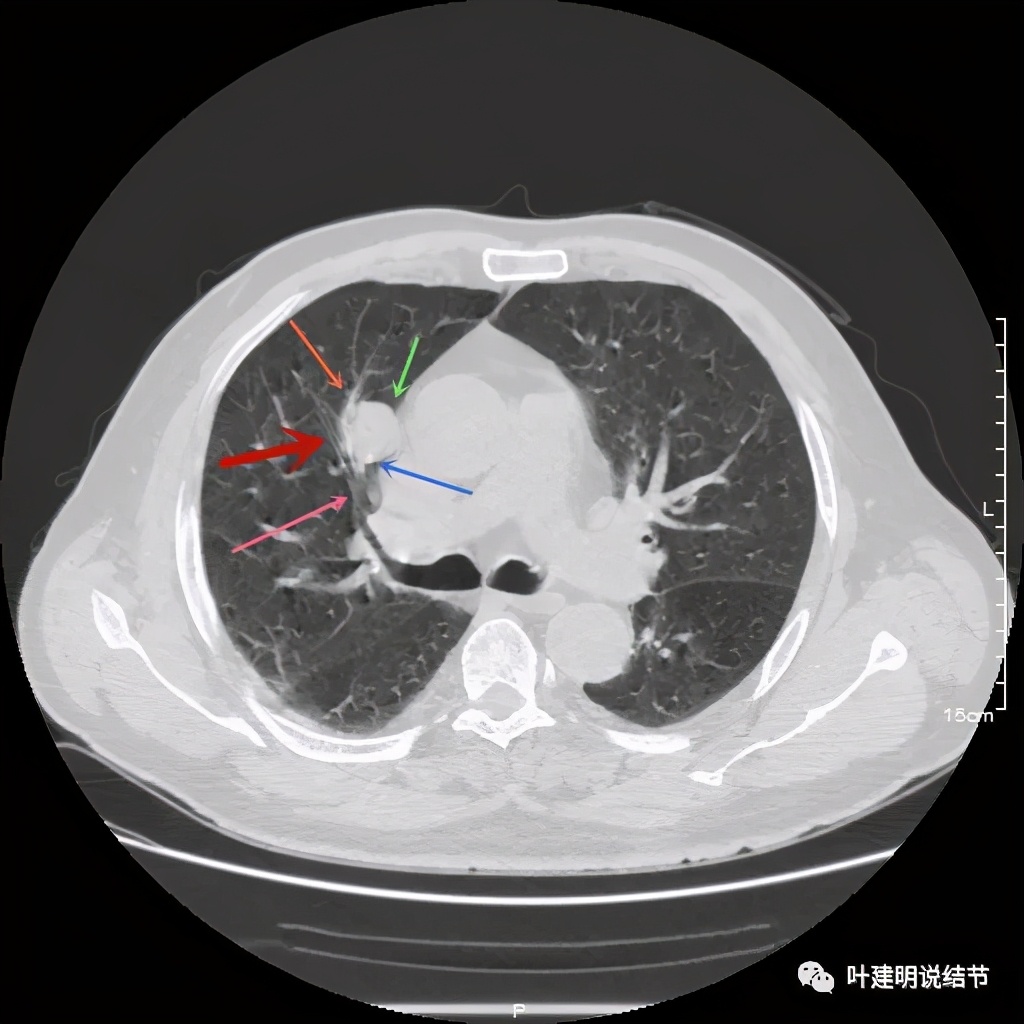

上图示病灶边缘过于光滑(绿色);局部有点状钙化(蓝色)

上图示病灶边缘过于光滑(绿色);血管贴边(桔色);

上图示病灶边缘过于光滑(绿色);血管贴边走行(桔色)

以上几图也示病灶边缘过光(绿色);血管贴边,感觉没受侵犯(桔色)